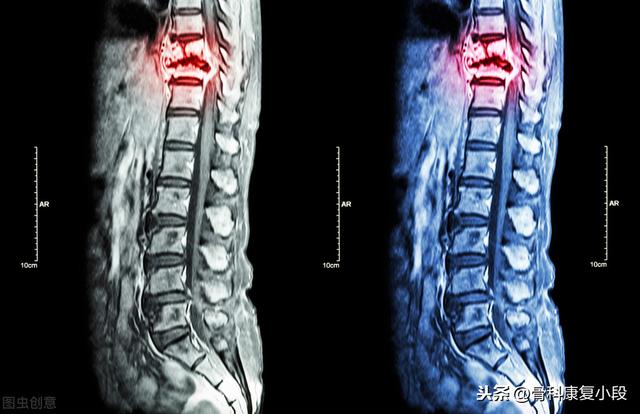

Quel type de douleur doit alerter sur la présence de métastases osseuses ? Les métastases osseuses sont une manifestation fréquente des tumeurs malignes à un stade avancé. La tumeur primaire présente dans d'autres parties du corps se métastase dans les os par les voies sanguines et lymphatiques, formant ainsi des métastases osseuses. Les métastases osseuses signifient que le tissu osseux normal a été détruit et remplacé par du tissu tumoral. Les métastases osseuses peuvent être classées en trois types selon la spécificité de la lésion : le type ostéolytique, le type ostéogénique et le type mixte. Les sites courants de métastases osseuses sont l'os de la diaphyse moyenne (colonne vertébrale et bassin), les côtes et la métaphyse inférieure, l'os de la diaphyse moyenne étant le plus courant, ce qui est lié aux caractéristiques de l'apport sanguin dans cette zone. Comme le montre le cercle ci-dessous, les métastases osseuses sont multiples et la colonne vertébrale est en mauvais état.

Montrant un cancer avec métastases osseuses survenant dans la colonne vertébrale thoracique